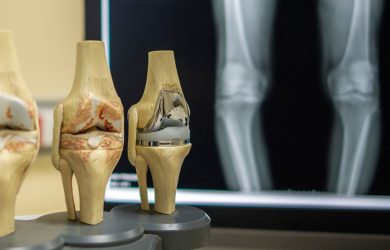

Ревізійне ендопротезування кульшового суглоба — це хірургічна операція, при якій раніше встановлений ендопротез кульшового суглоба частково або повністю